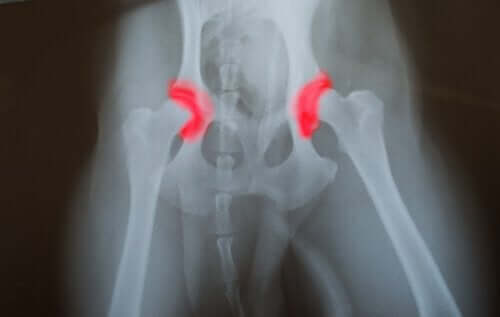

- Dysplazja stawu biodrowego

W porównaniu z innymi dużymi psami, których dieta nie była zbilansowana, te odpowiednio karmione zapadały na mniej chorób związanych z przerostem. Dysplazja stawu biodrowego była jedną z najczęściej występujących chorób u dużych, przekarmionych psów.

Przekarmianie dorosłych zwierząt powoduje szereg różnych problemów zdrowotnych. Pogorszenie się stanu ich stawów wydaje się być jednym z najczęstszych objawów u starszych psów.